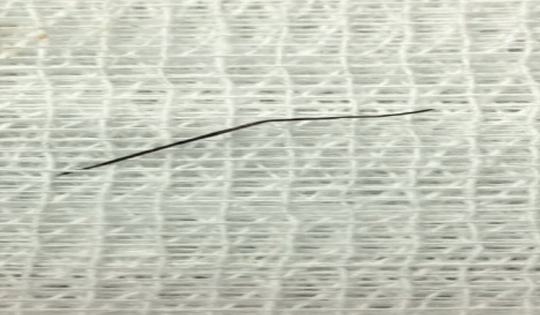

Thanh niên 20 tuổi ở Vĩnh Phúc thủng ruột non do gặp sự cố khi ăn lẩu

Bác sĩ đã phát hiện 2 dị vật trong lòng ruột bệnh nhân, chọc thủng thành ruột gây tình trạng nhiễm trùng trong ổ bụng.

Thủng ruột non do nuốt phải dị vật khi ăn lẩu

Sau bữa ăn lẩu, nam thanh niên 20 tuổi đau bụng âm ỉ, vài ngày sau sốt, vào viện thăm khám được đưa đi mổ cấp cứu.